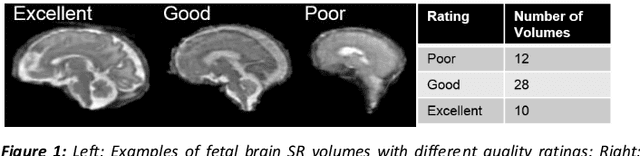

It is critical to quantitatively analyse the developing human fetal brain in order to fully understand neurodevelopment in both normal fetuses and those with congenital disorders. To facilitate this analysis, automatic multi-tissue fetal brain segmentation algorithms are needed, which in turn requires open databases of segmented fetal brains. Here we introduce a publicly available database of 50 manually segmented pathological and non-pathological fetal magnetic resonance brain volume reconstructions across a range of gestational ages (20 to 33 weeks) into 7 different tissue categories (external cerebrospinal fluid, grey matter, white matter, ventricles, cerebellum, deep grey matter, brainstem/spinal cord). In addition, we quantitatively evaluate the accuracy of several automatic multi-tissue segmentation algorithms of the developing human fetal brain. Four research groups participated, submitting a total of 10 algorithms, demonstrating the benefits the database for the development of automatic algorithms.